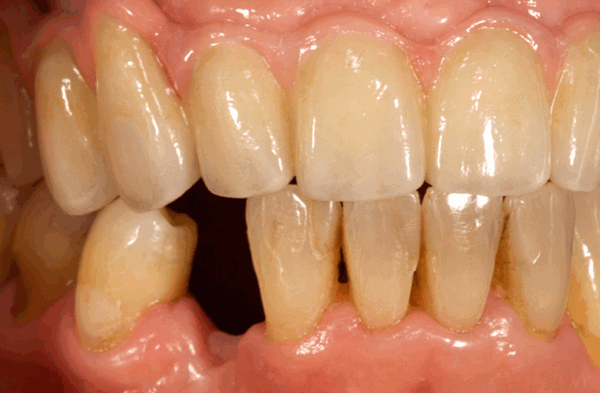

Перелом, вывих и удаление соседнего зуба возникает в результате использования щипцов с более широкими щечками, чем коронка удаляемого зуба. Это наблюдается и при неправильном использовании элеваторов для удаления зубов, например, если элеватором опираются на пятый зуб при удалении шестого или на второй зуб при удалении третьего, то можно вывихнуть или поломать менее прочный зуб. Данное осложнение следует отнести скорее к врачебным ошибкам.

В зависимости от вида травмы, нанесенной соседнему зубу, проводится его лечение (изготовление вкладок, коронок, штифтового зуба, удаление или реплантация зуба, укрепление зуба шиной).

Перелом и вывих соседнего зуба может произойти, если этот зуб поражен кариозным процессом или недостаточно устойчив и его используют в качестве опоры во время работы элеватором. При переломе соседнего зуба надо решить вопрос о целесообразности его сохранения и возможности дальнейшего консервативного лечения. При неполном вывихе следует укрепить зуб шиной, при полном вывихе - произвести реплантацию.

Если во время удаления переломился зуб, который располагался рядом с удалённым, врач оценивает, насколько разумно и возможно его сохранить. При незначительном повреждении возможно наращивание повреждённого участка. Если перелом серьёзный, зуб удаляется.

Не редки во время операции случаи вывиха ближайшего к удалённому зуба. При травмировании высокой степени показана реплантация. Если подвижность зуба сохранена, его укрепляют стабилизатором в виде эндо-донтоэндооксальным имплантом. При полной смерти тканей зуба проводят удаление с заменой на искусственный зуб. Если вывих неполный, проводится укрепление с использованием шины.